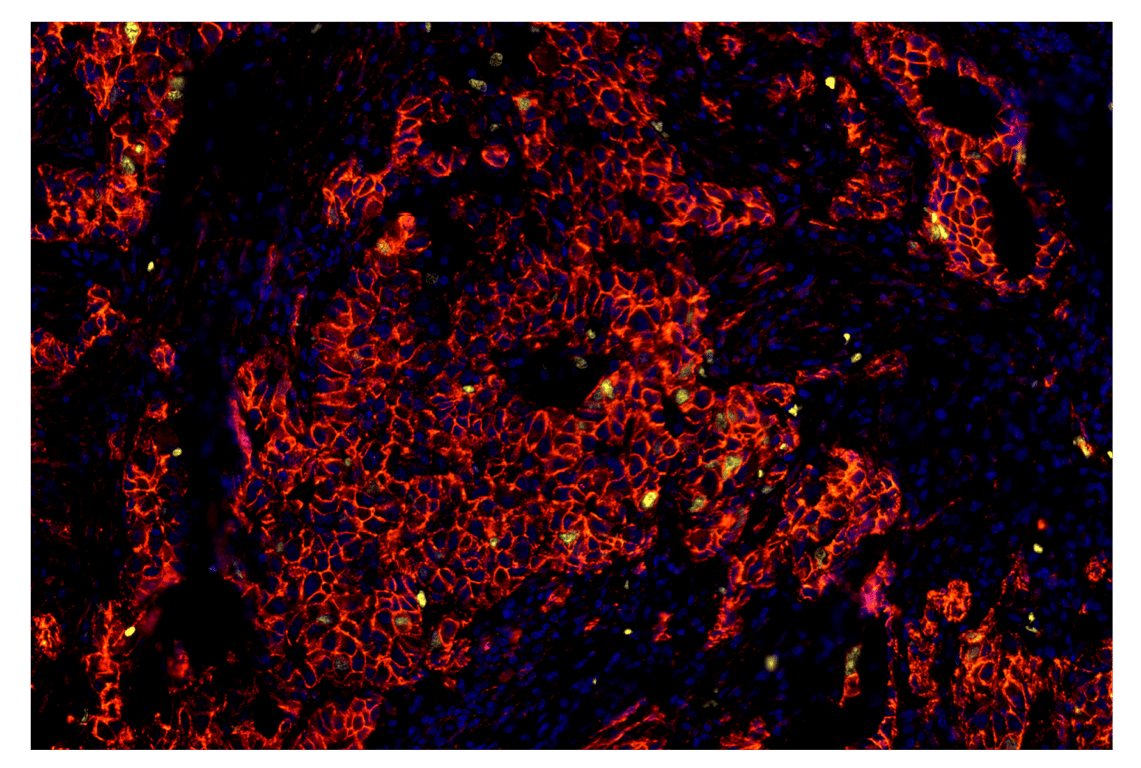

SignalStar™ multiplex immunohistochemical analysis of paraffin-embedded human squamous cell lung carcinoma using β-Catenin (D10A8) & CO-0108-594 SignalStar™ Oligo-Antibody Pair #83149 (yellow), CD40 (D8W3N) & CO-0115-647 SignalStar™ Oligo-Antibody Pair #39704 (red), and DAPI #4083 (blue). All fluorophores have been assigned a pseudocolor, as indicated.

Immunohistochemistry Image 2: beta-Catenin (D10A8) & CO-0108-750 SignalStar<sup>™</sup> Oligo-Antibody Pair